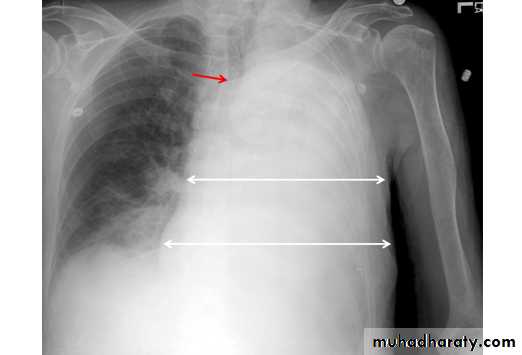

Pneumothorax

Pneumothorax refers to the presence of gas (air) in the pleural space. When this collection of gas is constantly enlarging with resulting compression of mediastinal structures it can be life-threatening and is known as a tension pneumothoraxIt is useful to divide pneumo thoraces into three categories :

Radiographic features

Chest radiograph

A pneumothorax is, when looked for, usually relatively easily appreciated. Typically they demonstrate:

visible visceral pleural edge see as a very thin, sharp white line

no lung markings are seen peripheral to this line

the peripheral space is radiolucent compared to adjacent lung

the lung may completely collapse

the mediastinum should not shift away from the pneumothorax unless a tension pneumothorax is present

A tension pneumothorax

A tension pneumothorax occurs when intrapleural air accumulates progressively in such a way as to exert positive pressure on mediastinal and intrathoracic structures. It is a life threatening occurrence requiring rapid recognition and treatment is required if cardiorespiratory arrest is to be avoided.Radiographic features

A pneumothorax will have the same features as a run-of-the-mill pneumothorax with a number of additional features, helpful in identifying tension. These additional signs indicate over expansion of the hemithorax:

ipsilateral increased intercostal spaces

shift of the mediastinum to the contralateral side

depression of the hemidiaphragm

tension pneumothorax